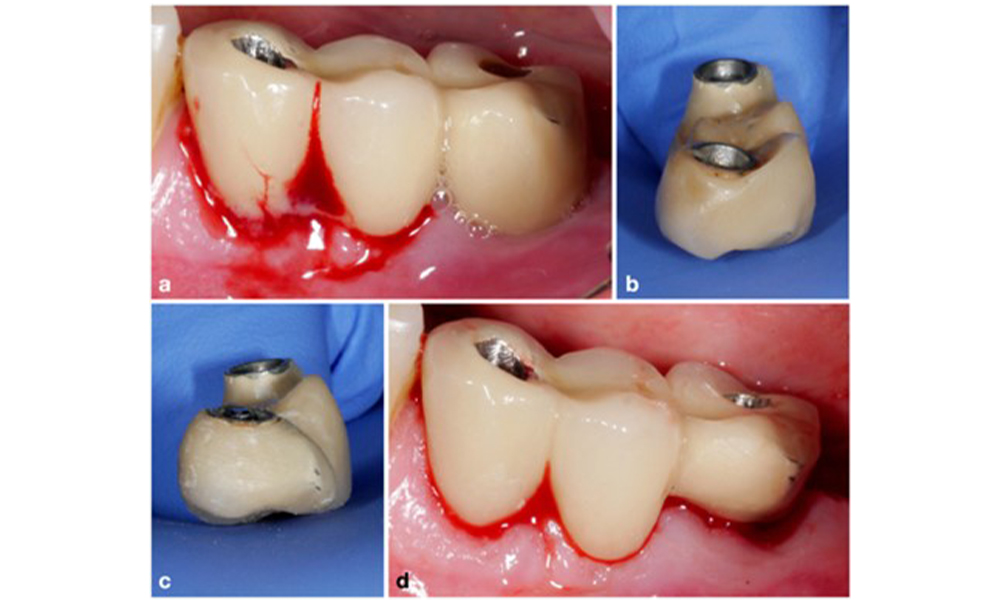

Modification of an existing bridge restoration. If the restoration hinders sufficient oral hygiene measures (notice the extreme overhang on the buccal aspect of the molar) (a–b), one of the first treatment steps should be adjusting the prosthetic design to enable effective cleaning (c–d).

Figure 5. Modification of an existing bridge restoration. If the restoration hinders sufficient oral hygiene measures (notice the extreme overhang on the buccal aspect of the molar) (a–b), one of the first treatment steps should be adjusting the prosthetic design to enable effective cleaning (c–d).